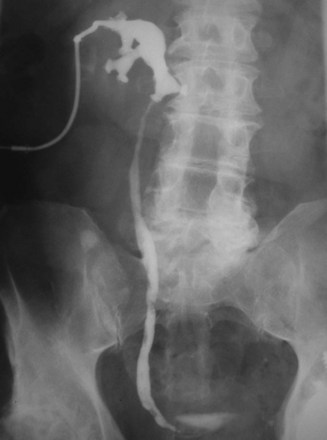

For patients with larger calculi or for those who demonstrate evidence of poor urine drainage, PNL should be the primary approach. The results of PNL for patients with calculi in a horseshoe kidney are generally superior to those achieved with SWL, with an average stone-free rate of 84% (range, 75% to 100%) (Esuvaranathan et al, 1991; Jones et al, 1991a; Al-Otaibi and Hosking, 1999; Raj et al, 2003; Shokeir et al, 2004). The optimal point of entry for these kidneys is through a posterior calyx, which is typically more medial than in the normal kidney because of the altered renal axis and rotation associated with the midline fusion (Fig. 48–5). Except in the isthmus of the horseshoe kidney, where the vascular supply can vary, vessels tend to enter the kidney anteriorly. An upper pole collecting system puncture is often appealing because the entire kidney is usually subcostal. In most cases the lower pole calyces are anterior and inaccessible percutaneously. During PNL the flexible nephroscope often aids in accessing stones within anteromedial calyces, which may be difficult to reach with a rigid nephroscope.

Figure 48–5 Antegrade nephrostogram performed after percutaneous nephrolithotomy of a horseshoe kidney via an upper pole access. Note the subcostal nature of the access and the unique calyceal orientation inherent in a horseshoe kidney.